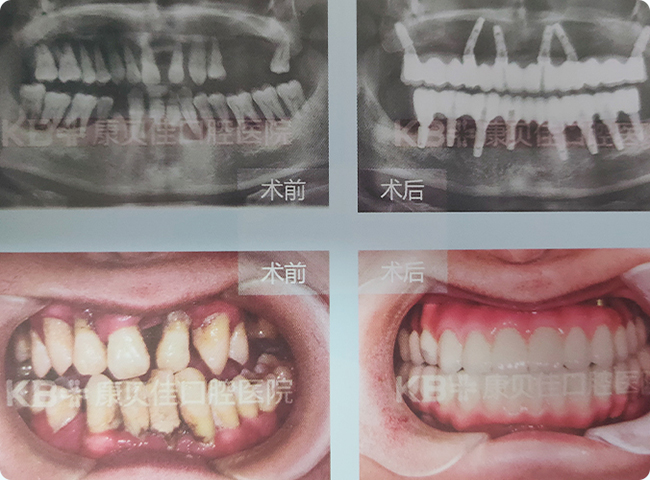

何先生 50岁

几年前牙齿开始松动、脱落,经过对比选择康贝佳做了全口种植。上半口采用种植6颗修复半口技术,下半口采用种植4颗修复半口技术。

治疗方案:

上颌种植6颗修复半口 下颌种植4颗修复半口